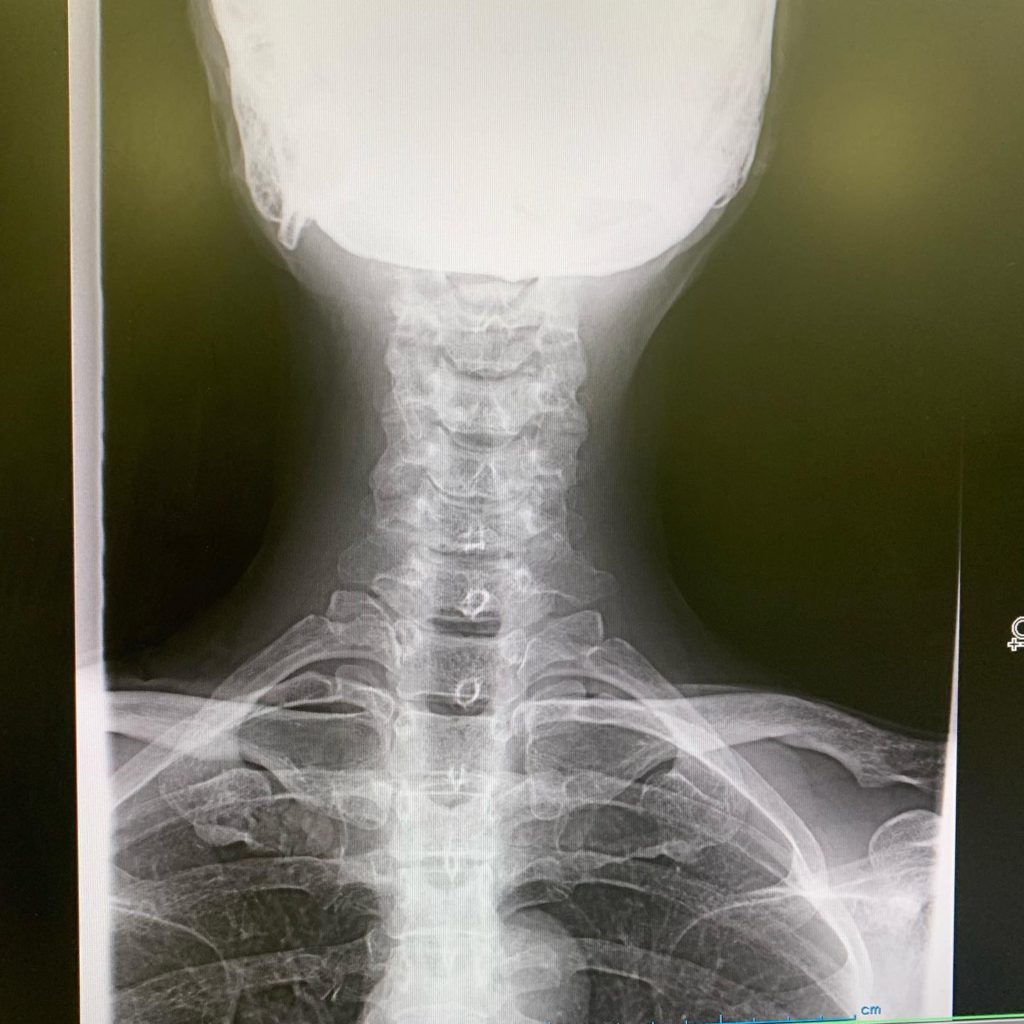

レントゲン撮ったら、首は真っ直ぐ過ぎるし、椎体は骨棘できて変形してるし、椎間板も減ってるし。